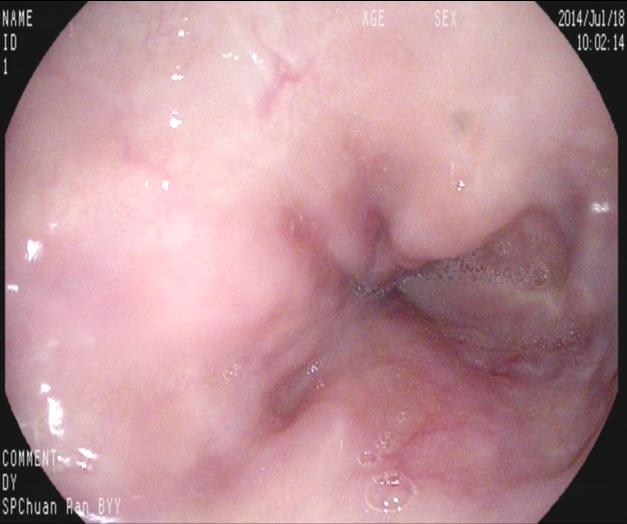

【九個(gè)月后復(fù)查】

九個(gè)月來(lái)患者無(wú)黑便及嘔血,復(fù)查胃鏡,食管內(nèi)曲張靜脈基本消失,胃底曲張靜脈亦減輕?;颊咴俅纬鲅L(fēng)險(xiǎn)而減低。如下圖:

上4圖隱構(gòu)可見(jiàn)套扎后癍痕,及右上方時(shí)鐘1點(diǎn)鐘位置略充盈的靜脈,無(wú)紅色征,不連續(xù)。